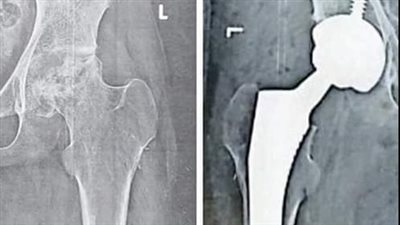

جراحة ناجحة لتغيير مفصل كامل لفخد طفلة بمنظومة التأمين الصحي الشامل ببورسعيد

نجاح عملية تغيير وتركيب مفصل بمنظومة التأمين الصحي الشامل ببورسعيد (صور)